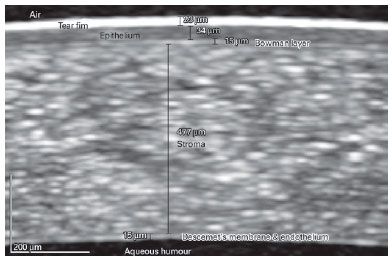

Figure 1 shows an example of the method by which we measured the thicknesses of the tear film and the layers of the cornea. Thickness measurements for the cornea and sclera were performed manually using caliber tools provided within the Spectralis software. We used a 600-800% zoom to analyze the images and recorded measurements of the pre-ocular tear film and corneal layers at the center of the cornea. Anterior scleral thickness measurements were performed at 1 mm and 3 mm from the limbus (Figure 2). The conjunctiva was eliminated to precisely measure the scleral thickness. The scleral curve was considered while drawing a measurement line for examinations at 3 mm; to maintain standardization only the temporal sclera was chosen in the analysis for all the participants.

Only one eye from each participant was randomly selected for this analysis. We used the anterior segment module of the spectral-domain OCT (Spectralis software, version 6.0, Heidelberg, Germany) to measure tear film thickness, corneal layer thickness, and anterior scleral thickness. For viewing and analyzing the anterior segment structures, the Spectralis uses an add-on lens and software with an 8-16-mm scanning width and 3.9-µm axial resolution.